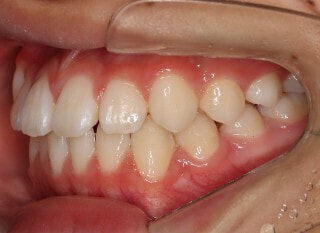

小児期第一段階

終了時